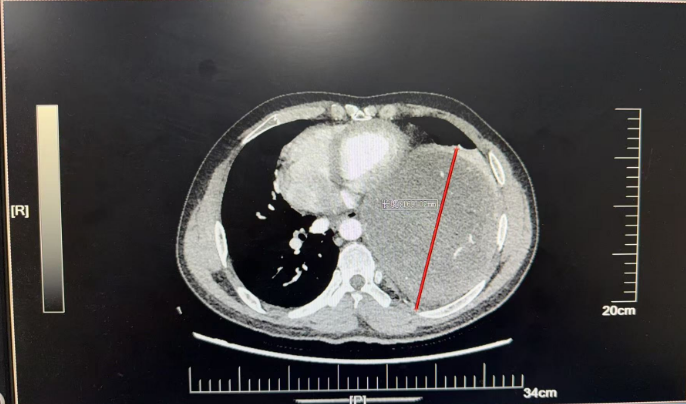

近日,北京天坛医院胸外科团队在多学科协作下,历经4小时,成功为患者完整切除左侧胸腔内直径近19厘米的巨大神经鞘瘤。此次手术的顺利完成,不仅彰显了北京天坛医院胸外科的精湛技术,更体现了多学科协作在疑难重症救治中的关键作用。

家中“顶梁柱”的杜先生,两个月前,左侧卧位时频繁出现心慌、胸痛等症状,当地医院检查后发现,其左后纵隔-胸腔内存在巨大占位性病变。进一步穿刺活检提示为“梭型细胞瘤,结合免疫组化考虑神经鞘瘤”,当地医院虽为其进行了射频消融治疗,暂时缓解了症状,但因肿瘤体积过大、位置特殊,手术切除难度极高,无法开展根治性治疗。

为寻求一线生机,杜先生通过熟人介绍并结合网上查询,慕名找到北京天坛医院胸外科主任医师杨增。医院胸CT检查结果令人揪心,成年人一侧胸腔宽度大约10-15厘米,而杜某的肿瘤直径近19厘米,占据了左侧多半个胸腔,把心脏和主动脉都挤偏了,原本竖直的主动脉已经弯到了右侧。再继续发展,一旦压迫到降主动脉,就会引发急性心衰,随时可能猝死。但更棘手的是,如果进行手术,该肿瘤为实性肿瘤,无任何囊变,血运极其丰富,且与左肺下叶致密粘连,甚至可能累及脊髓,手术中稍有不慎就可能导致心脏骤停、心律失常、大出血、截瘫等严重并发症。“不能因为风险高就放弃患者。”杨增了解情况后,当即决定将患者收入院。